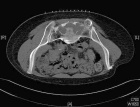

45 year old female with three month history of pain in low back radiating to left lower extremity

Zoom image: Radiological image Radiological image.